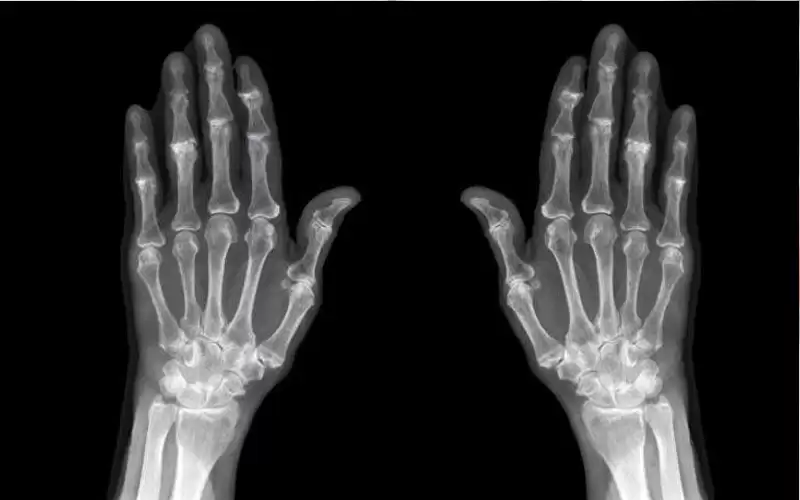

ما أسباب هشاشة العظام؟